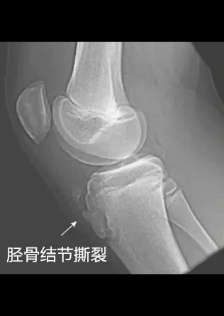

膝盖下方的部位就是上图的红色区域,这块红色区域是髌骨下方,主要有两个结构:髌韧带和胫骨粗隆,胫骨粗隆也被叫做胫骨结节。在询问病史和查体后,基本可以确定孩子患上了髌韧带损伤或胫骨结节损伤,为了进一步确认,让孩子做了X线检查,检查图像如下。

从图片中我们可以观察到孩子的胫骨结节已经撕裂,并见有碎骨快,综合考虑孩子之前的症状,最终将孩子确诊为胫骨结节软骨病。那么什么是胫骨结节软骨病呢?

一般多发于12-14岁之间的孩子,好动的男孩比女孩更容易患此病。胫骨结节软骨病一般只在一侧发病,两侧同时发病的概率较小。具体的症状表现为:胫骨结节处有压痛并且在运动时会加剧疼痛,但是皮肤却不会出现红肿的现象。在X光的照射下,会明显看见胫骨结节骨骼增大或撕裂,就像上面那张孩子拍的X光图片。了解了胫骨结节软骨病的症状和特点后,我们该如何治疗呢?